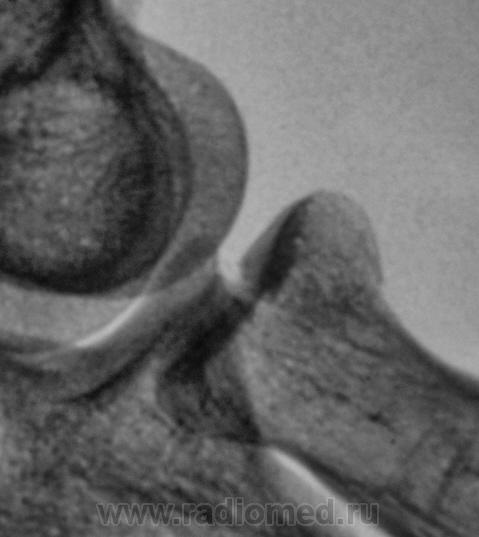

Фрагменты с увеличением.

Предположу продольный перелом головки луча с допустимым смещением.